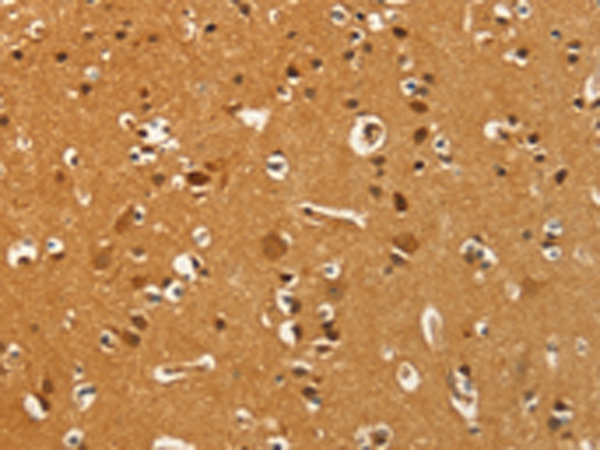

分类: 科研抗体货号: P04663别名:应用: WB,IHC反应种属: Human, Mouse, Rat